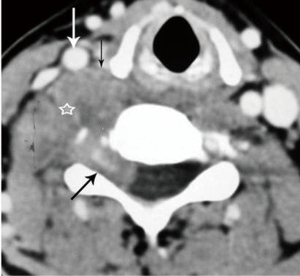

Due to its location between the vein and artery in the carotid space, schwannomas of the vagus nerve tend to separate the artery and vein, usually displacing the CCA/ICA medially and the IJV laterally (Figures 2,3) (12). Some schwannomas of the vagus nerve may displace the IJV and ICA/CCA in a posterior direction without splaying them and there is usually separation between the artery and vein (Figure 4). The cervical sympathetic chain runs in a fascial reflection posterior and slightly medial to the carotid space. Hence, schwannomas of the sympathetic chain tend to displace the IJV and CCA/ICA together, usually anteriorly and laterally (Figure 5) (5). A large schwannoma of the sympathetic chain may distort the surrounding anatomy and result in a posterior displacement of the carotid vessels without separation of the artery and vein (Figure 6) (13,14). Occasionally, a schwannoma of the cervical sympathetic chain may splay the internal and external carotid arteries at the carotid bifurcation but without encasing the arteries (Figure 7) (5). In these regards, the position of the tumor relating to the vessels in the carotid space is more important than the direction of vascular displacement. There has also been a reported case of schwannoma arising from the glossopharyngeal nerve in the carotid space causing posterior displacement of the ICA (15).